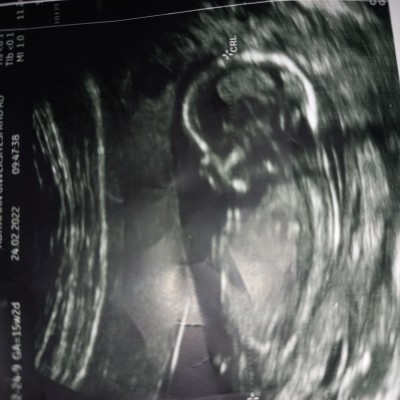

Ultrason fotosuna gore cinsiyet tahmini:)    Baska bi sayfada gordum bebegin durusuna ve pozisyona gire cinsiyett tahmini yapiliyormus. Ultrason goruntusune gore bebegimin cinsiyetini tahmin edebilecekler yorum yaparsa sevnrm

1. Ultrason resmini göre cinsiyet  nedir sizce doktor erkek dedi

image

15.haftalik sizce cinsiyet nedir

Sizce cinsetini nedir